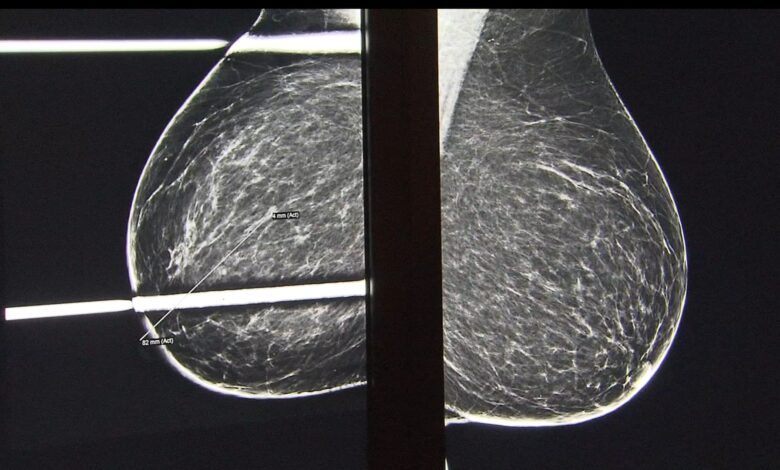

نوع خفيّ من سرطان الثدي يفلت من صور الماموغرام ويصيب حالة من كل عشر نساءعلوم وصحةنشر السبت، 25 أكتوبر تشرين الأول 2025نوع من سرطان الثدي يصعب اكتشافه في فحوص الماموغرام الروتينية، أصبح الآن أكثر انتشارًا. قراءة المزيدمرض السرطان